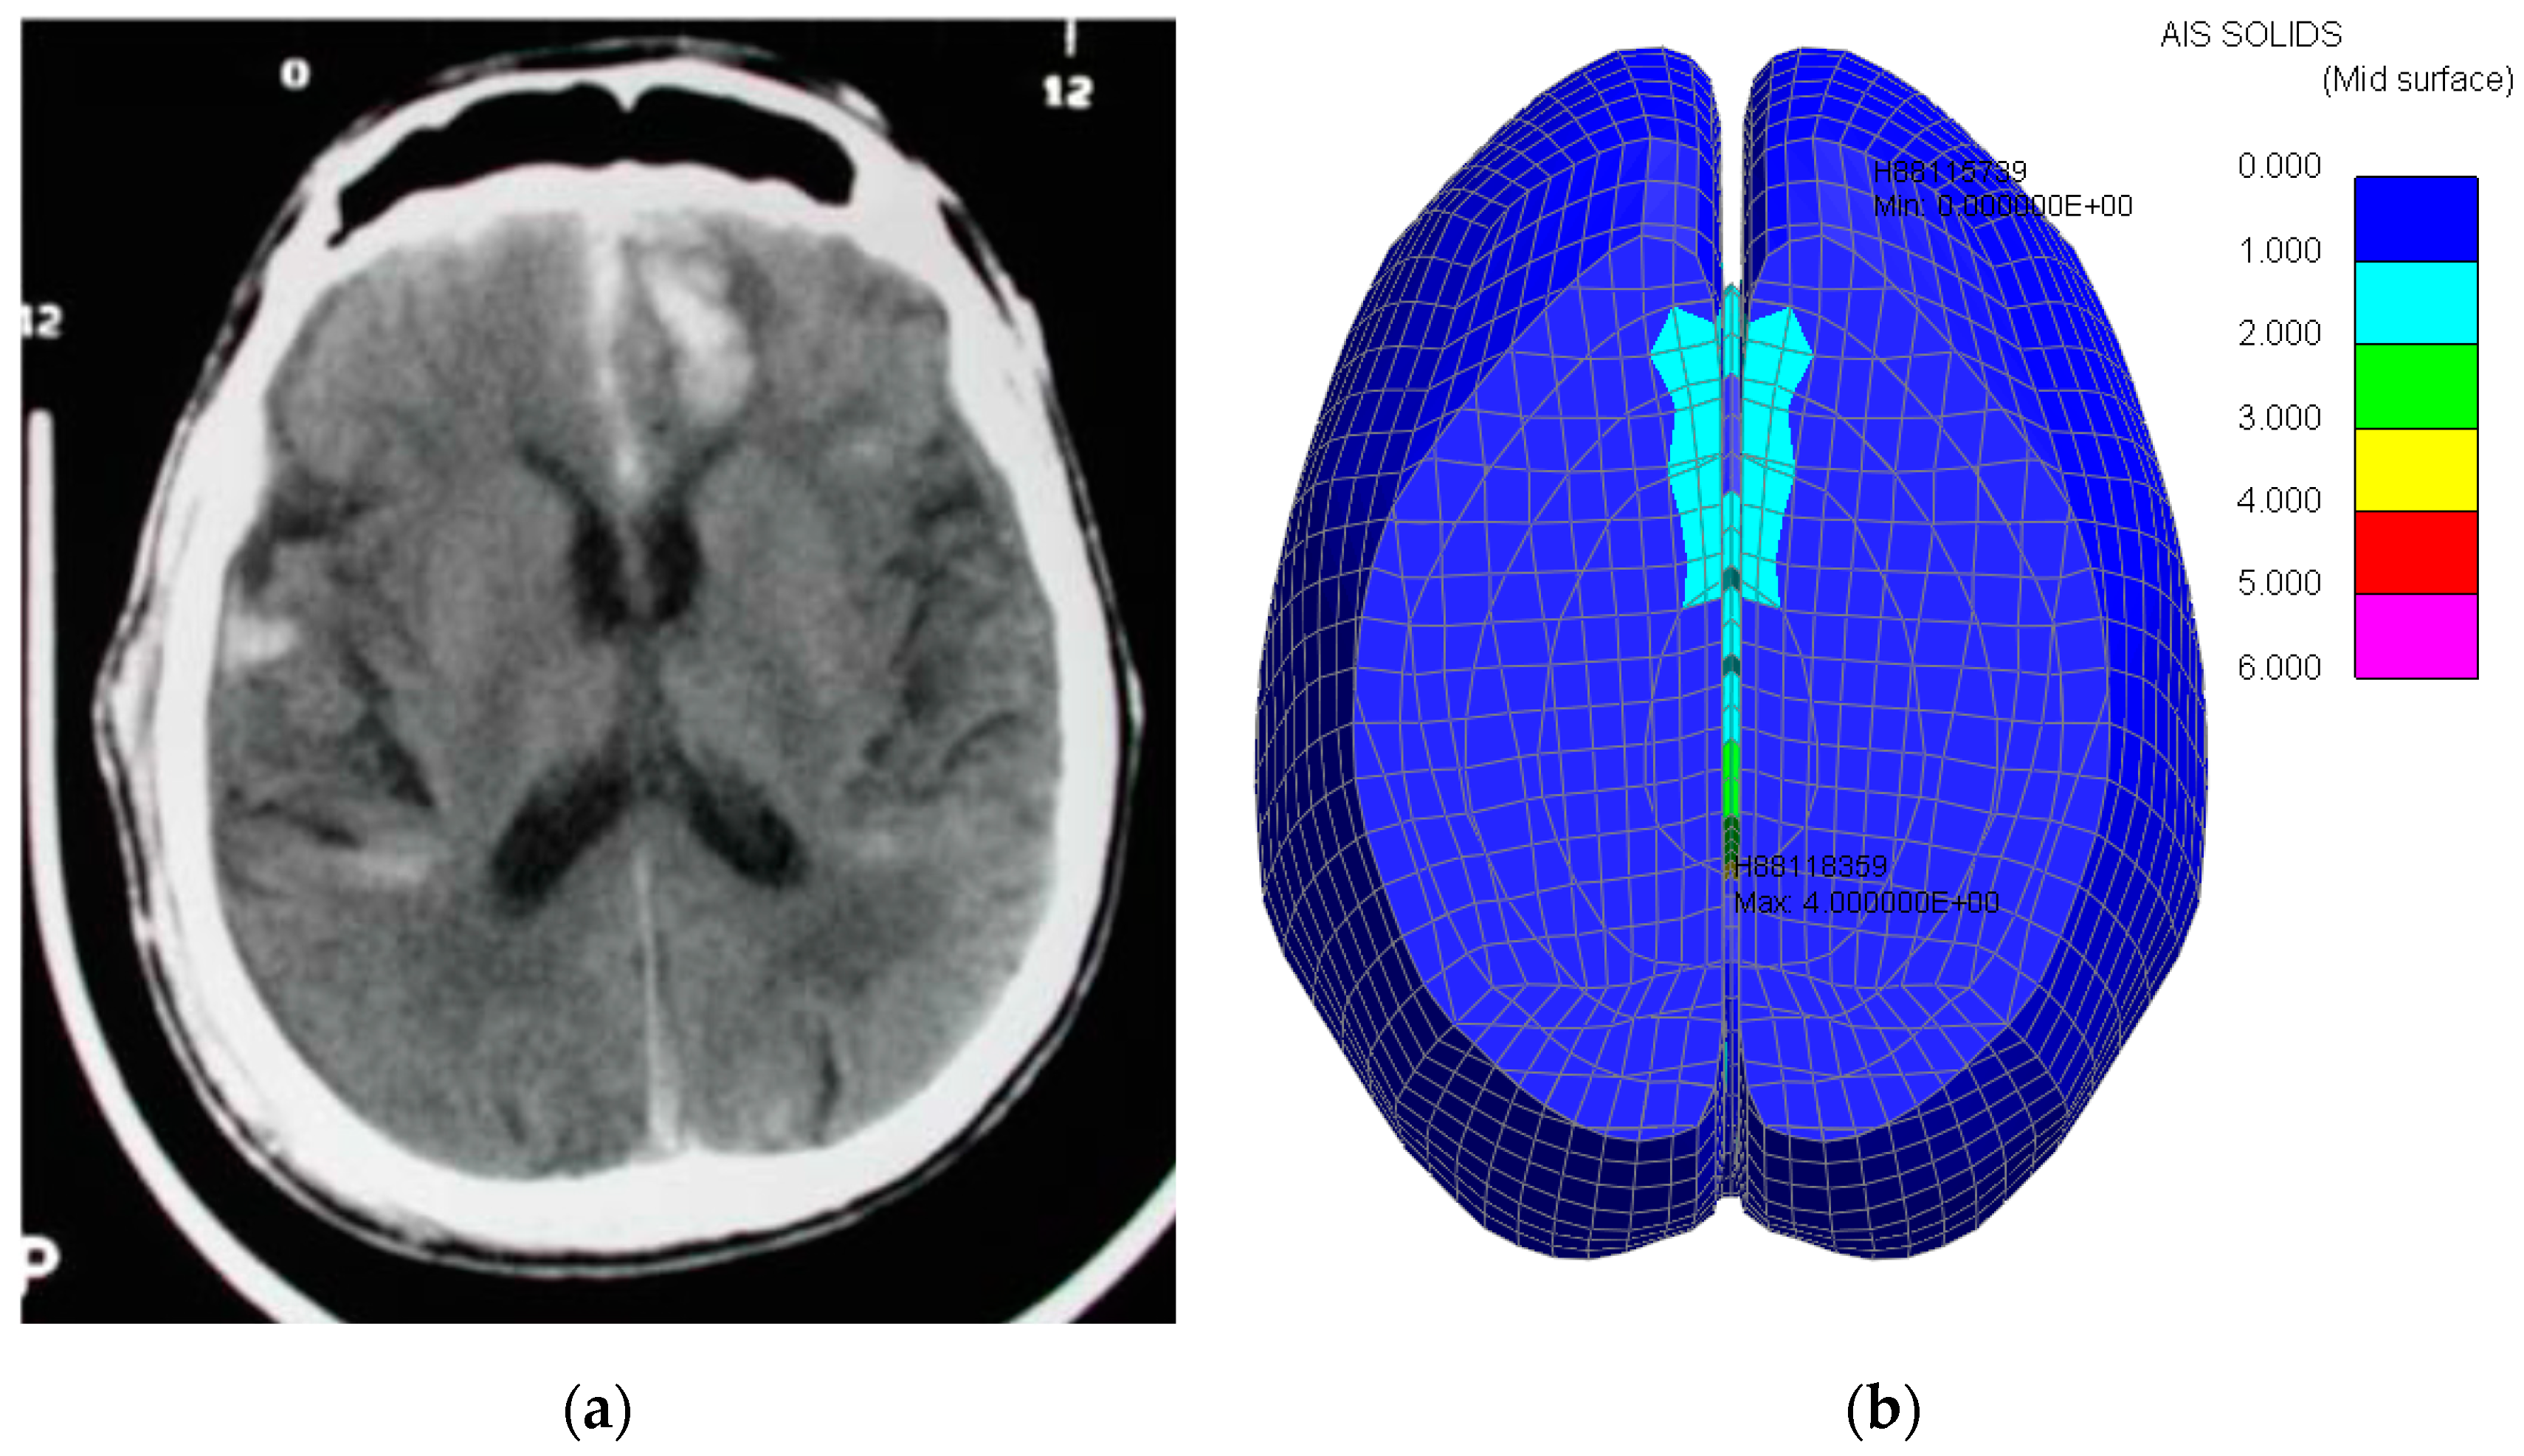

The PVP value computed was 0.05 mW, which is overlaid over the OTM model for an impact speed of 1.5 m/s. The trauma severity is therefore AIS 1, as illustrated in Figure 12a.

Figure 12.

Parietal Grey Matter—OTM Model. (a) Parietal grey matter trauma prediction, (b) Maximum Principal strain (grey matter).

As the grey matter maximum principal strain did not exceed 25.5% (8.7%), the trauma severity remains unchanged, i.e., AIS 1 (Figure 12b).

3.2.2. White Matter

The PVP value computed was 0.07 mW, which is overlaid over the OTM model for an impact speed of 1.5 m/s. The trauma severity is therefore AIS 1, as illustrated in Figure 13a.

Figure 13.

Parietal White Matter OTM Model. (a) Parietal white matter trauma prediction, (b) Maximum Principal strain (white matter).

As the grey matter maximum principal strain did not exceed 25.5% (8.4%), the trauma severity remains unchanged, i.e., AIS 1 (Figure 13b).